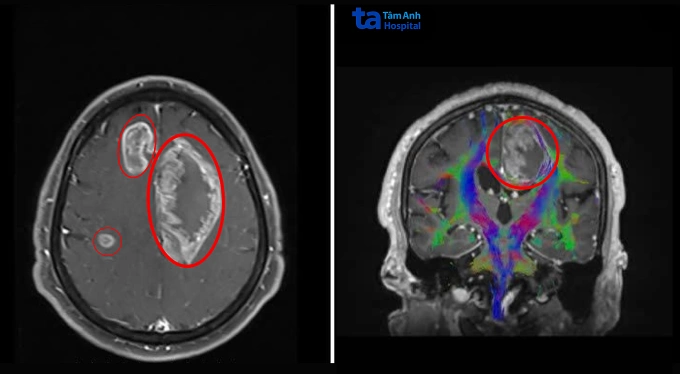

Ông Giang có biểu hiện nói bất thường từ hai tháng trước, gần đây tay chân yếu nên cầm đồ vật bị rơi và đi lại loạng choạng, đến Bệnh viện Đa khoa Tâm Anh TP HCM khám. Kết quả chụp MRI 3 Tesla ghi nhận ông Giang có đến ba khối u nằm trong não. Khối lớn nhất ở thùy trán trái, kích thước lớn như quả cam, 7 cm. Hai khối u nhỏ hơn 3,5 cm và 1,3 cm ở thùy trán và thùy đỉnh phải.

Ảnh chụp MRI 3 Tesla ghi nhận ba khối u lớn (khoanh tròn) trong não ông Giang. Ảnh: Bệnh viện Đa khoa Tâm Anh

"Trường hợp u não đa ổ như ông Giang phức tạp do các khối u nằm sâu, lan rộng qua cả hai bán cầu đại não", ThS.BS.CKII Chu Tấn Sĩ, Trưởng khoa Phẫu thuật Thần kinh, Trung tâm Khoa học Thần kinh, nói, thêm rằng các ổ u xâm lấn vào thân thể chai (trung tâm truyền tín hiệu liên bán cầu), chèn ép não thất bên trái và đè lên các đường dẫn truyền thần kinh quan trọng như bó tháp (kiểm soát vận động). U nằm gần những vùng chức năng nhạy cảm liên quan đến ngôn ngữ, vận động và hành vi, nếu không được xử lý sớm, u phát triển có thể làm tăng áp lực nội sọ, tụt não, hôn mê, tử vong.